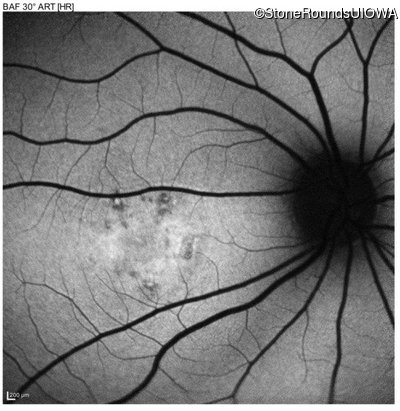

AR Stargardt Disease (IIA)

Age at visit: 20 years

Age at visit: 22 years

This 20 year old man first noticed some difficulty reading the board at school in 9th grade 20 in 2017